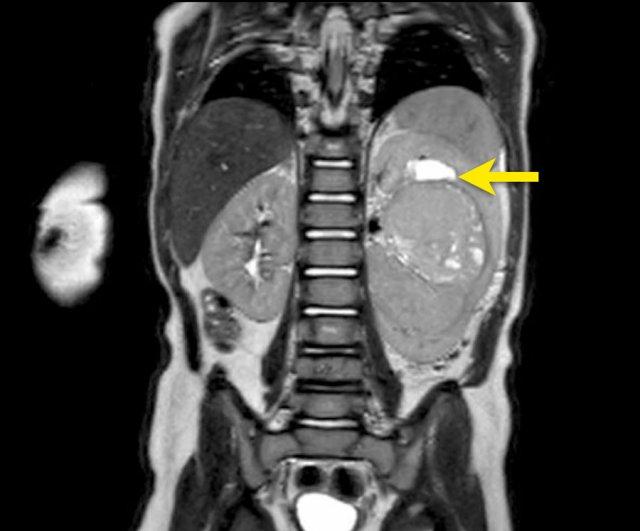

Mức độ lan rộng của khối u được đánh giá rõ ràng trên chuỗi xung TSE T2 weighted 3D theo mặt phẳng axial.

The left kidney is compressed and displaced caudally.

Có di căn hạch bạch huyết cạnh động mạch chủ (mũi tên vàng nhỏ).

Nguyên ủy của thân tạng và động mạch mạc treo tràng trên bị khối u bao quanh (đầu mũi tên).

Tĩnh mạch chủ dưới bị đẩy ra phía trước (mũi tên xanh).

Xẹp phổi hai bên ở vùng lưng thường được thấy trên MRI, vì việc kiểm tra được thực hiện dưới gây mê.